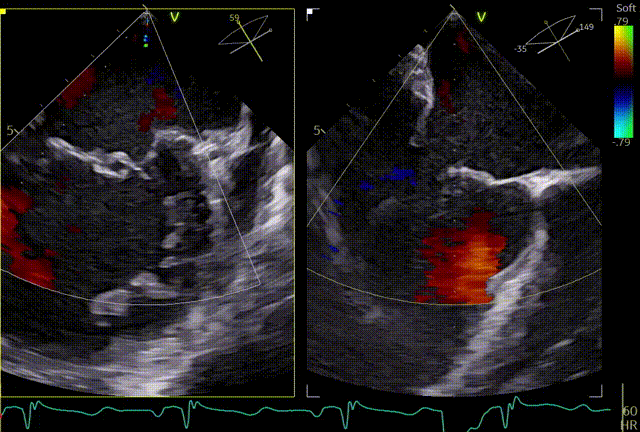

术前TEE及左房压

1区

1区带彩

2区

2区带彩

3区

3区带彩

3D

3D带彩

术前肺静脉频谱

3区gap

术前左房压